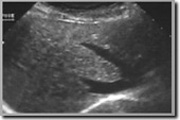

Les ultrasons permettent d’examiner n’importe quel tissu du corps, à condition qu’il ne soit pas « caché » derrière un os ou de l’air, par exemple. Le principal avantage de l’échographie est qu’elle n’est pas invasive. En fait, cela ne fait pas mal.

![]() | Détecter les accumulations de liquide (kyste vbn., hémorragie,…) |

![]() | Pour évaluer la forme et la taille des organes internes (par exemple, la rate, le foie, le pancréas, les reins, l’appendice,…) |